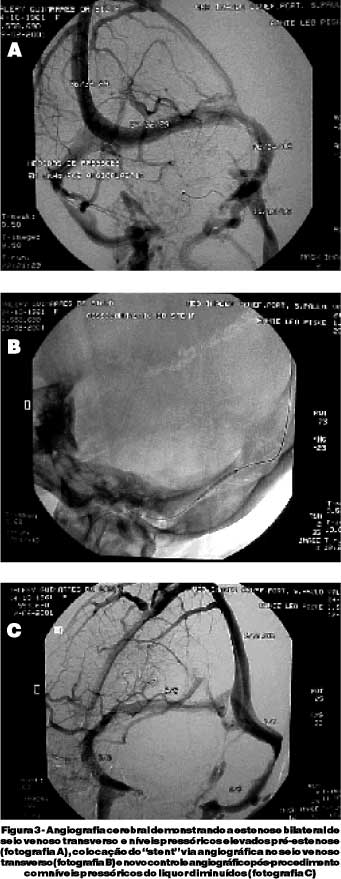

A tomografia computadorizada (TC) e a ressonância magnética (RM) do encéfalo apresentaram-se sem alterações significativas, demonstrando sinais de hipertensão intracraniana e provável estenose bilateral dos seios transversos. A angiografia cerebral confirmou estenose grave na transição do terço médio com o distal de ambos os seios transversos, havendo comprometimento luminar de aproximadamente 50% (figura 3). No cateterismo venoso, a pressão do golfo jugular, foi de 9 mmHg à direita e 8 mmHg, na porção inicial dos seios transversos foi 28 mmHg à direita e 31mmHg, na porção distal do seio sagital superior de 45 mmHg.

A paciente foi submetida a implante de "stent" via angiográfica do tipo "Velocity" de 4,5 mm de diâmetro x 20 mm de comprimento (figura 3), evoluindo com melhora significativa do quadro de cefaléia, restauração dos níveis pressóricos à normalidade (pressão média de 7 mmHg no seio sagital superior, 6 mmHg no seio transverso esquerdo e 5 mmHg no seio sigmóide esquerdo) após o procedimento (figura 3). Houve melhora da campimetria computadorizada (figura 2) e da acuidade visual (20/30 em ambos os olhos) e o controle angiográfico demonstrou regressão importante da estenose com boa luz ao nível do "stent" após dois meses do procedimento intervencionista. Neste mesmo período, houve diminuição da hiperemia e do edema de papila, sendo observada maior nitidez das bordas papilares, à fundoscopia, que se mantiveram nos exames subseqüentes após quatro meses da intervenção radiológica, apresentando acuidade visual corrigida de 20/25 em ambos os olhos, não constando alterações campimétricas e os níveis pressóricos estavam compatíveis com a normalidade.